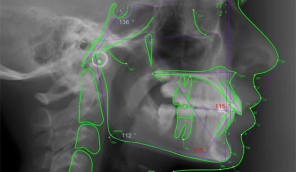

5. 40 Common Cephalometric Measures

7. Digitizing and Analysis of a Cephalometric Image

Lesson 30.45 - 40 Common Cephalometric Measures

Cephalometrics - Chapter Five- 40 Common Cephalometric Measures –written and produced by Dr. Robert Little and Dr. Rebecca Poling.

Presentation: 60 minutes Run Time, Knowledge Quiz: 48 Questions5 CE Credits

Goal: Your goal in this chapter will be to learn the 40 commonly used cephalometric measurements. These are but a small sample of the measurements that have been proposed since the cephalometer was first introduced in the early 1930’s. Understanding these presented in this lesson will prepare you to easily grasp other measurements that may be preferred in your practice.

The 40 measures are:

All of the quizzes of this chapter are to help you learn these common measures and become familiar with measurements that are “normal” so that you will recognize when you look at a ceph radiograph, you will see where there is a problem, even without measuring the ceph. When you are an experienced clinician, you will be able to look at a patient, suspect which relationships are not “normal” and then confirm your suspicions with a cephalometric analysis.

The most important concepts to take away when you learn this module is that you must identify and correctly measure or digitize the 40 basic measures listed in this lesson. You also must know the name of each measure, the abbreviation of it, the construction of it, the calculation of it, the meaning or diagnosis of the result, and the limits that might make the measure less accurate. This is a lot of detail, but once you understand the meaning of these 40 common cephalometric measures you will be have much more expertise in diagnosis of the relationships of the hard and soft tissues of the skull.